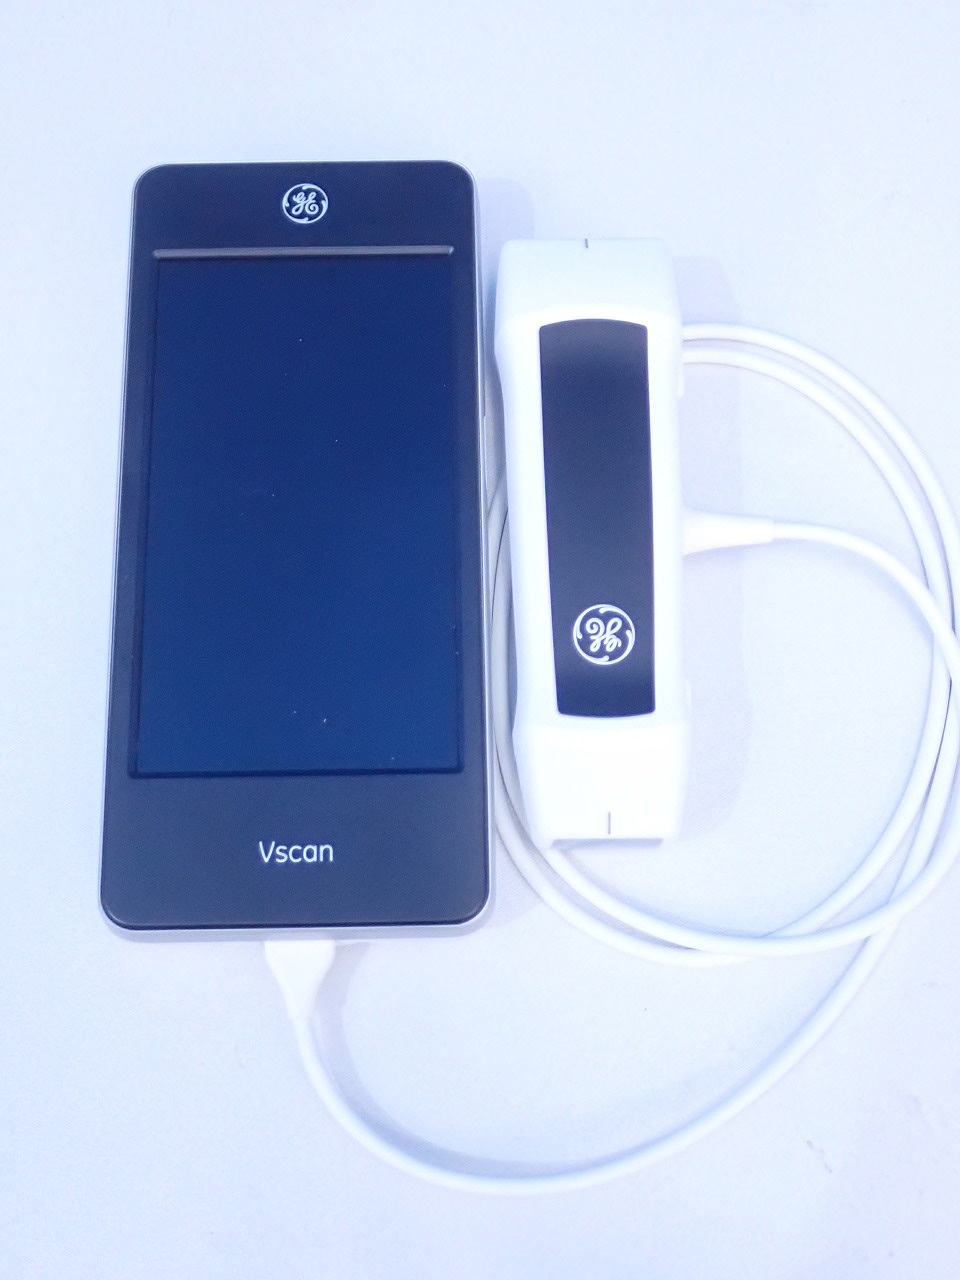

TOSHIBA PLE-705S型 リニア式電子スキャンプローブ エコー 超音波診断装置 東芝の詳細情報

カテゴリビューティー、ヘルスケア救急、衛生用品その他状態傷や汚れあり(詳細)■商品名:PLE-705S型 リニア式電子スキャンプローブ

■メーカー:TOSHIBA